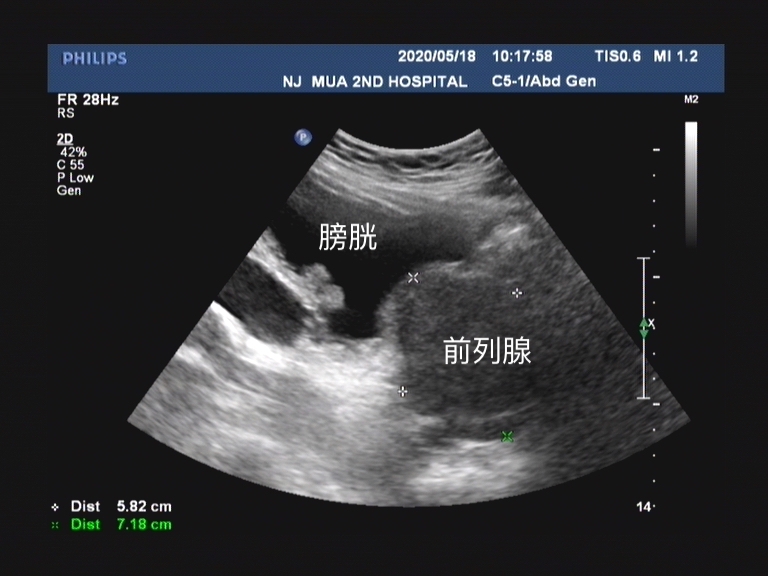

前列腺动脉栓塞是 通过数字减影血管造影显示前列腺动脉的解剖结构,通过栓塞前列腺供血动脉,使前列腺组织缺血萎缩,从而达到缓解下尿路症状的目的。

手术方式由于是 局部麻醉 ,所以对患者身体情况要求不高,很多不能耐受外科手术的患者也就有了新的方式。手术部位是 股动脉 ,通过盆腔血管造影,观察髂内动脉和前列腺动脉,通过栓塞剂栓塞前列腺动脉。

任何一个组织需要存活,那必不可少的一个条件就是由血供支持。 前列腺的营养血管是前列腺动脉,大部分前列腺供血动脉是双侧对称的。 但是值得注意的一点就是,无论是国内还是国外研究都统一认为, 前列腺动脉起源、分布和吻合支情况差异很大!